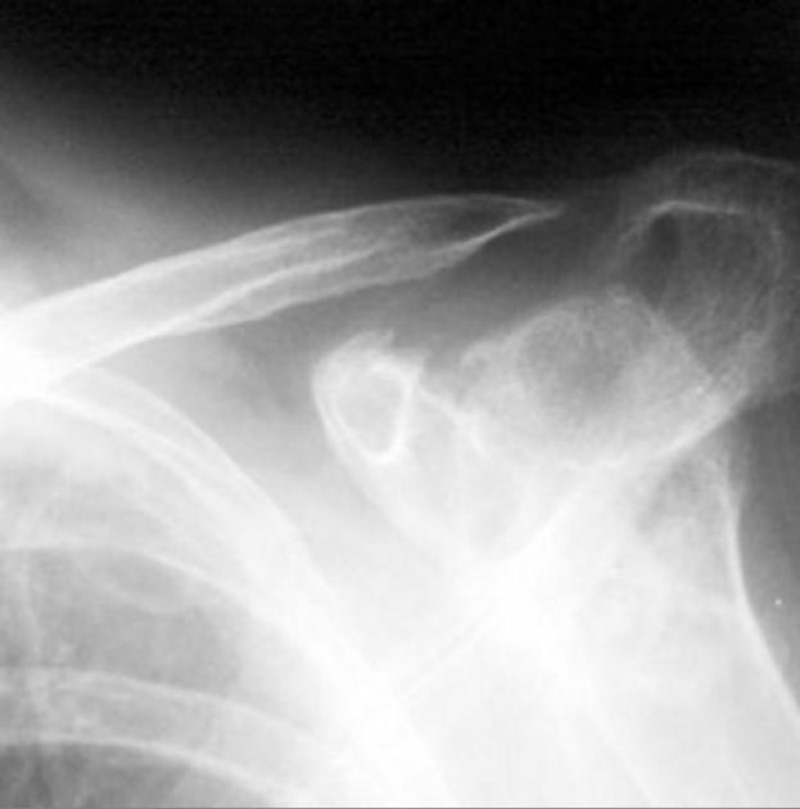

Bệnh viêm khớp dạng thấp gây sưng, cứng, trật khớp và xuất hiện các nốt dạng thấp ở khuỷu tay, khiến người bệnh khó cử động cánh tay hoàn toàn:

Một số hình ảnh chụp X-quang viêm khớp dạng thấp: